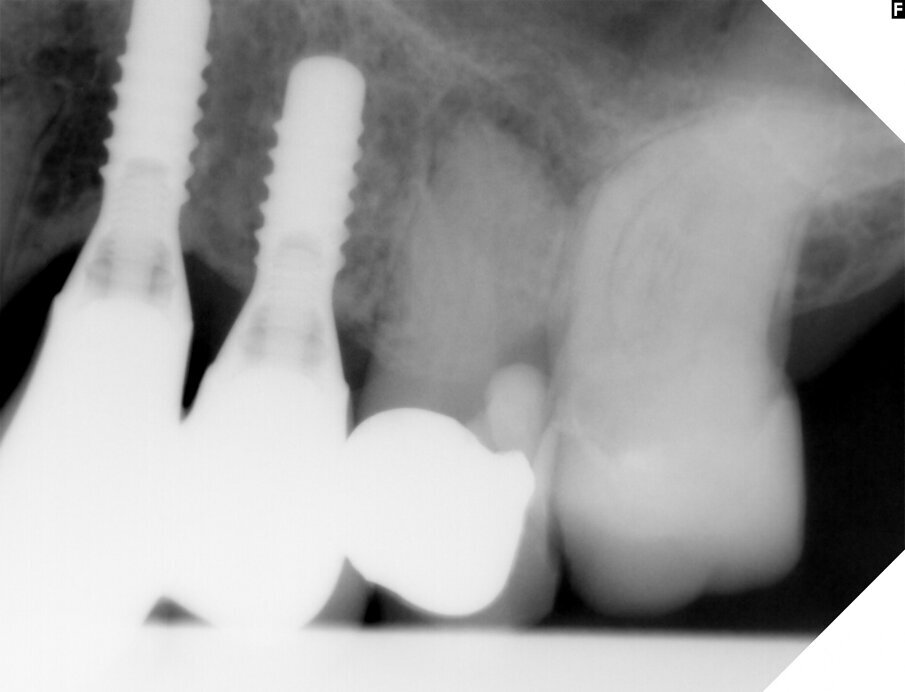

A 76-year-old female patient visited our clinic owing to pain in the left maxilla. She had a fistula in the buccal gingiva between tooth #25 and position #24. There were implants in positions #24 and 23. Tooth #25 already had a crown. The tooth had been affected by secondary caries earlier and had been repaired. A periapical radiograph showed an active inflammatory process in progress from the endodontically treated tooth that greatly worsened the prognosis and could have adversely affected the implants. The prognosis was therefore considered poor and we decided to extract the tooth.

Fig. 1: The radiograph showed an ongoing pathological process in the bone in the apical area of the root.

Fig. 2: Fluoroscopy by insertion of a gutta-percha point showed apical destruction as the source of infection.